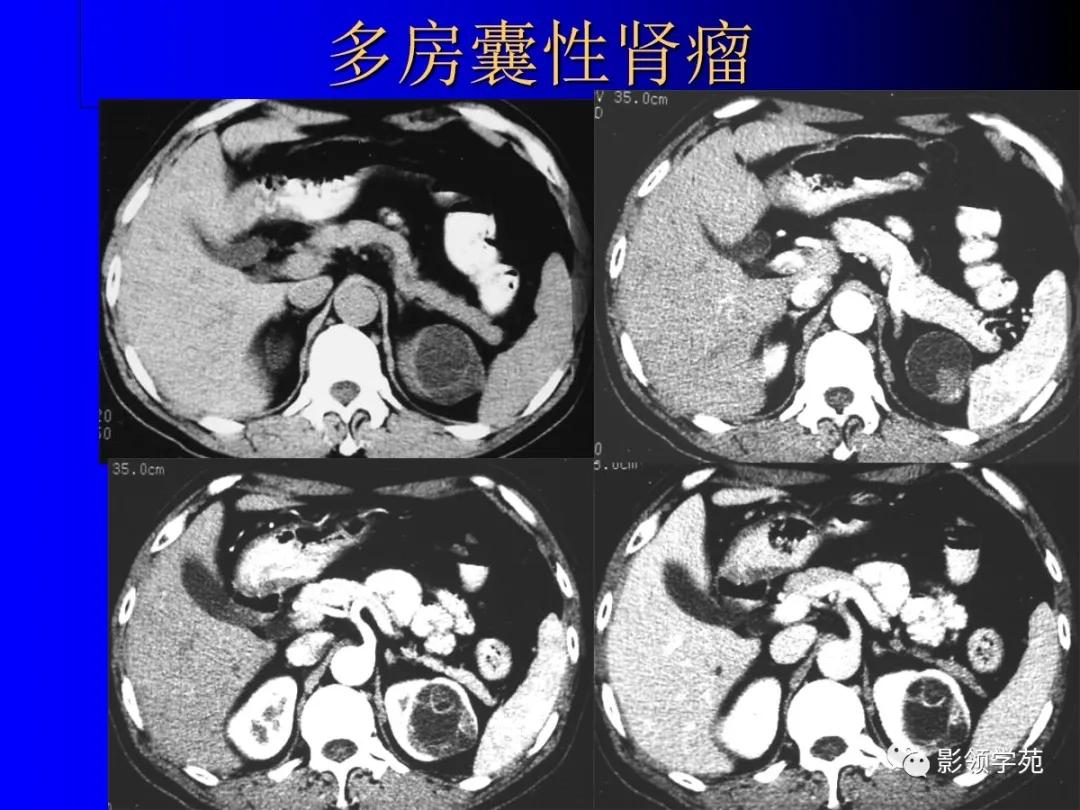

4、多房囊性肾瘤multilocular cystic nephroma

非遗传性的囊性病变。

囊壁内衬立方或扁平上皮。

多房囊腔间互不交通,伴完整的纤维分隔。

恶性者即多房囊性肾癌。

12、肾癌囊变和多房囊性肾癌

多房囊性肾癌有完整分隔

3、囊性肾癌的CT表现

囊性肾癌的CT表现各异,根据本组影像结果显示,囊性肾癌主要有以下CT表现:

(1)平扫囊内平均CT值较单纯囊肿偏高,约15~20 HU,而单纯囊肿CT值 一般为10 HU以下。

(2)囊壁连续性中断,向邻近肾实质浸润低密度影。

(3)囊壁厚薄不均,有向囊内或囊外凸出的壁结节,可明显强化。

(4)部分囊壁模糊。

(5)平扫囊内密度不均者,增强扫描囊内可出现不均匀强化,CT值可达35 HU左右。

(6)冠状位后重建图像显示为不规则形囊性肿块。

(7)囊壁弥漫弧形钙化,良性单纯囊肿很少见,是否为囊性肾癌的典型征象尚有待商榷。